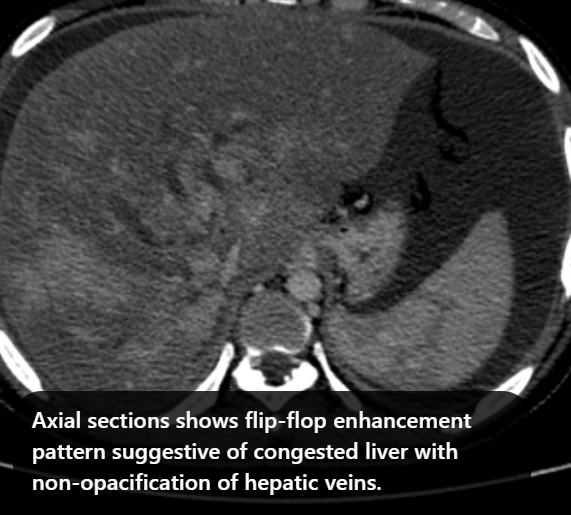

Clinical Case [Uncaptioned image] [Uncaptioned image]

Image Findings: The patient underwent contrast-enhanced computed tomography which showed features of a congested liver with flip-flop pattern of enhancement. Hepatic veins show hypoattenuation on delayed phase. An accessory hepatic vein is also noted in segment VI. A diagnosis of Budd Chiari syndrome (BCS) was made on the basis of the clinical and imaging features. The patient was referred to the interventional radiology team for an endovascular rescue. On conventional venogram, the diagnosis of BCS was confirmed as the hepatic veins were thrombosed. An accessory segment VI hepatic vein was noted draining into the IVC…